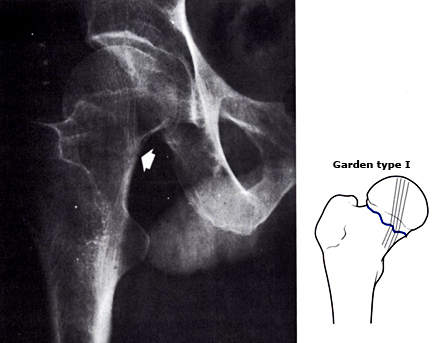

股骨颈(大胯)骨折,如果没有完全断开,或者断开的骨头茬(cha)子之间像两个齿轮的齿一样互相嵌插咬合在一起(我们称之为嵌插骨折),如下图。这时骨折断端之间还是有一定稳定性的。

白箭头所指处,即为股骨颈骨折部位,但因为嵌插而不明显

这个时候,患者虽然骨折了有点疼,但是却可以继续负重行走。很容易让患者误以为没有骨折,觉得只是软组织挫伤。